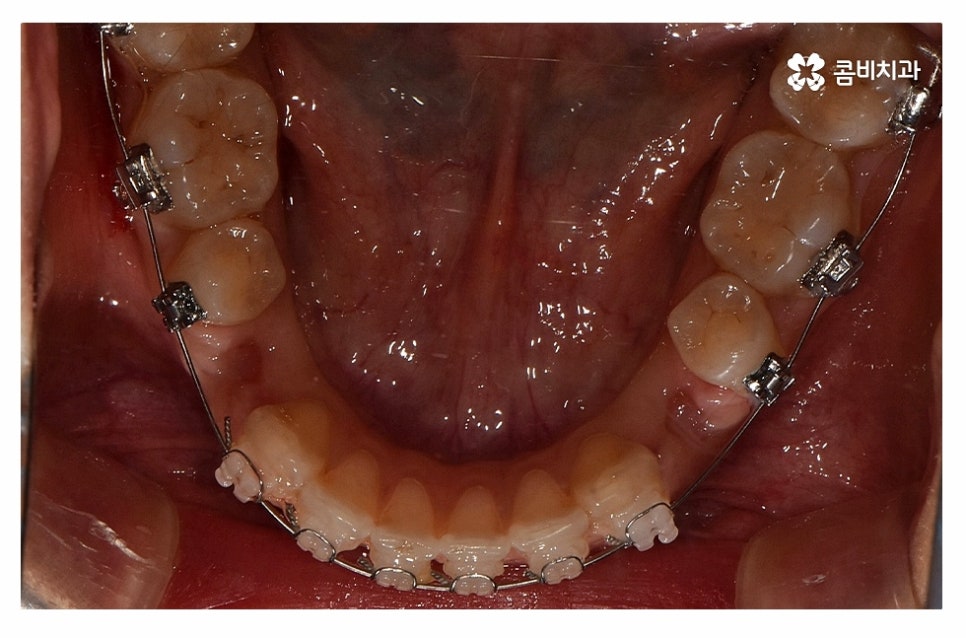

윗니는 설측교정으로 진행하고 아랫니는 일반적인 순측교정으로

치료를 진행하는 방식을 콤비교정이라고 부르고 있는데요.

보통 평소에 대화를 하고 웃을 때 윗니가 위주로 보이기 때문에

콤비교정은 심미적인 치료 방법이며 혀가 위치한 아랫니는

순측교정을 하기 때문에 발음상의 불리함이나 이물감 등에서

유리하기 때문에 합리적인 치료 방법이라고 할 수 있어요.